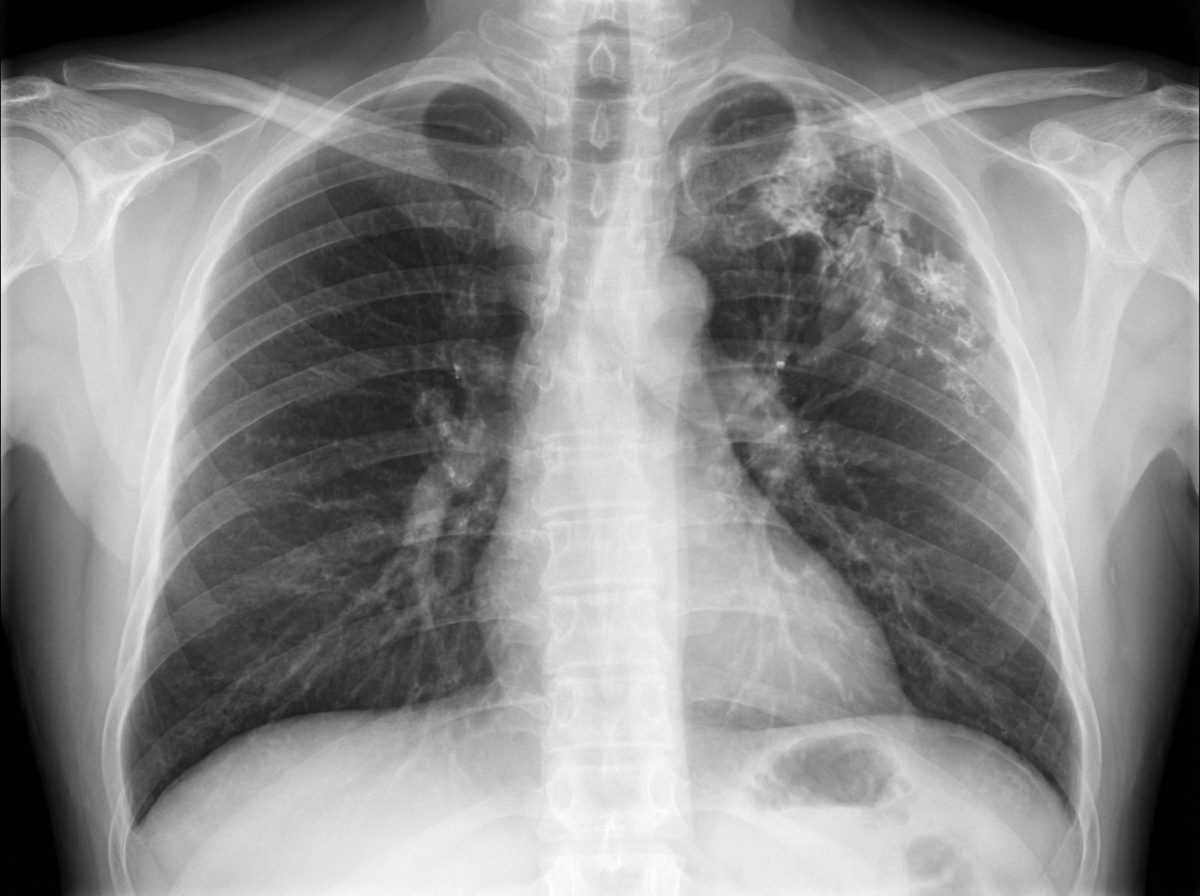

A 68-year-old female smoker presents to the ER with mild hemoptysis and cough, producing 1 to 2 teaspoons of light-green sputum daily. She uses inhalers as needed for occasional shortness of breath. A routine chest X-ray is obtained. What is the most likely cause of the abnormality seen on the CXR?

Explanation: ***Old tuberculosis with thoracoplasty*** - **Thoracoplasty** shows characteristic features of **absent upper ribs**, **asymmetric chest configuration**, and **apical volume loss** with possible **calcifications** from old TB. - This was a **pre-antibiotic era treatment** for tuberculosis, involving surgical removal of ribs to collapse the lung and control infection. *Asbestos exposure* - Would typically show **bilateral lower lobe** pleural changes like **pleural plaques** or **pleural thickening**, not upper lobe asymmetry. - **Pleural calcifications** in asbestosis are usually **bilateral** and **symmetrical**, unlike the unilateral changes seen in thoracoplasty. *Lung cancer* - Would present as a **discrete mass** or **nodule** on chest X-ray, not structural chest wall deformity. - Given the patient's smoking history and hemoptysis, cancer should be considered but wouldn't cause **rib absence** or **chest asymmetry**. *Chronic bronchitis* - Typically shows **hyperinflation** with **flattened diaphragms** and increased **anteroposterior diameter** on CXR. - Would not cause **structural chest wall abnormalities** or **rib absence** as seen in thoracoplasty cases.